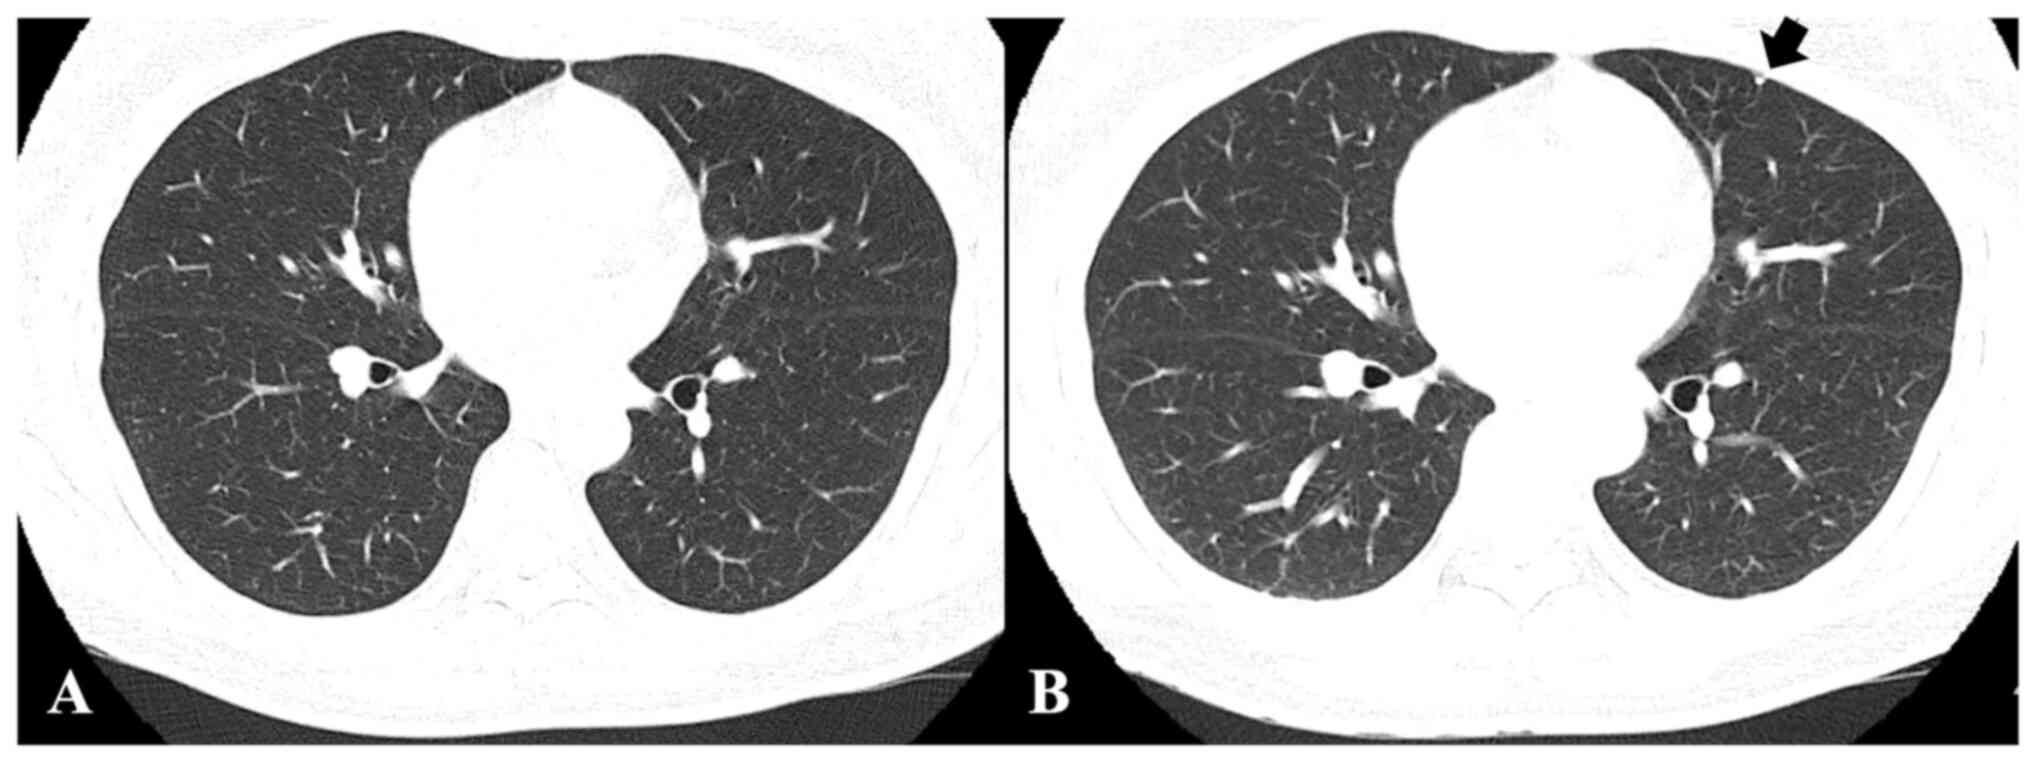

To meet the study purpose, radiographic images, namely CT, X-rays and magnetic resonance images were reviewed. CT images and chest X-rays were evaluated to confirm pulmonary metastasis. Follow-up chest CT images were screened for metastatic nodule development and progression to evaluate treatment efficacy. Follow-up chest CT images were analyzed to measure and evaluate the course of metastatic nodules receiving treatment. The chest CT evaluations determined whether the metastatic nodules were advanced, stationary or reduced (Fig. 1).

Figure 1.

Giant cell tumor of bone in the distal femur without pulmonary metastasis. Chest computed tomography at the (A) first visit and at (B) 12-month follow-up. At follow-up, the patient had a small nodule measuring 4 mm (black arrow) in the left posterior lower lung.